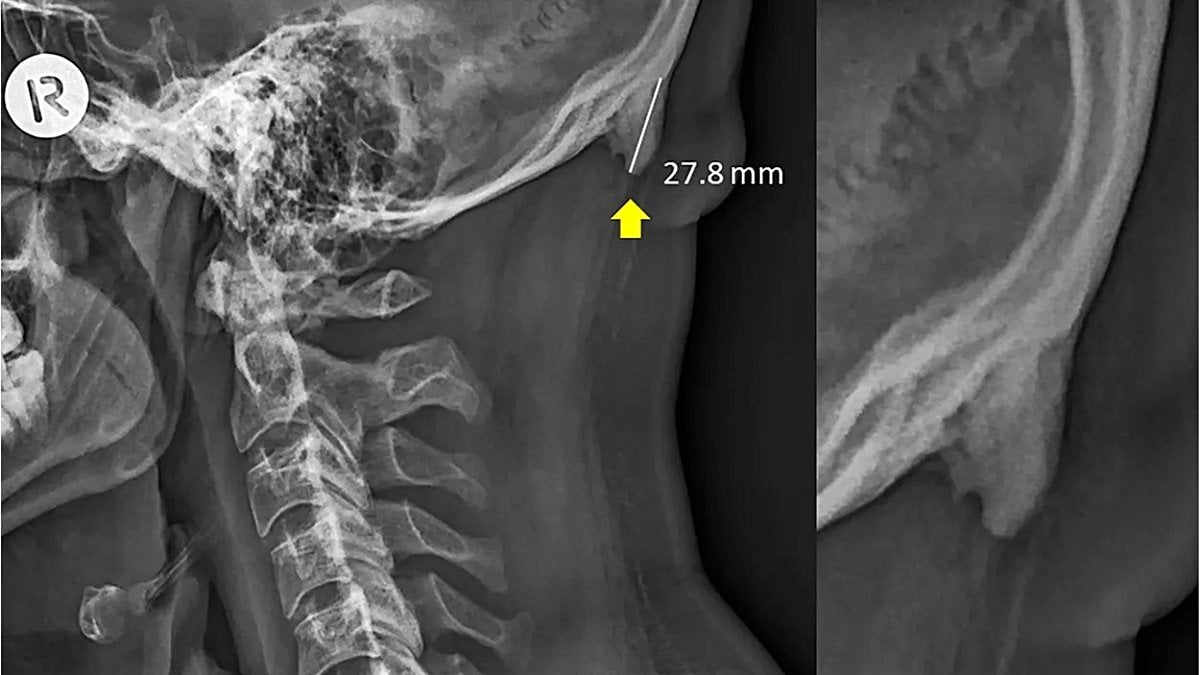

Söz konusu kemik uzantısını ortaya çıkaran veriler, 3 yıldır boyunca Avustralya'nın Queensland bölgesinde çekilen X-ışını taramalarından geliyor. Bu taramalarda, söz konusu çıkıntıların da bulunduğu bölgenin fotoğrafları çekildi. Normalde bu kemik uzantıları çok şaşırtıcı değil ve yaşlılarda görülüyor; çünkü yıllar yılı hayatta kalıp, boyun kaslarına yük bindirince, bu kemikler de ilerleyen yaşlarda gelişebiliyor. Ancak şaşırtıcı olan, genç yetişkinlerde de bu kemiklerin gözükmeye başlamış olması. Hem de kimi zaman bu genç yetişkinlerde yaşlılardan bile daha uzun kemikler görülüyor!

Genişlemiş dış oksipital çıkıklık (İng: external occipital protuberance) adı verilen bu durum eskiden gençlerde çok nadiren görülmekteydi. Ancak 2018 yılında Clinical Biomechanics dergisinde yayımlanan bir çalışma, bunun gençlerde daha sık görülmeye başlandığını ve sebebinin genetik veya enflamasyon gibi faktörler olmadığını; daha ziyade mekanik yük binmesi sonucu olduğunu gösterdi.

İşte bundan yola çıkan araştırmacılar, nihayetinde 18-86 yaş arası insanlara ait 1200 X-ışını taramasını inceleyerek, bu kemiklerin popülasyonun %33'ünde bulunduğunu ve şaşırtıcı bir şekilde artık yaş ilerledikçe bu kemiklerin kısaldığını gösterdiler! Bu keşif, yerleşik bilimsel bilgilerimizle fazlasıyla zıt. Çünkü normalde bu çıkıntılı kemiklerin ilerleyen yaşlarda daha da uzadığı düşünülmekteydi! Shahar şöyle diyor: